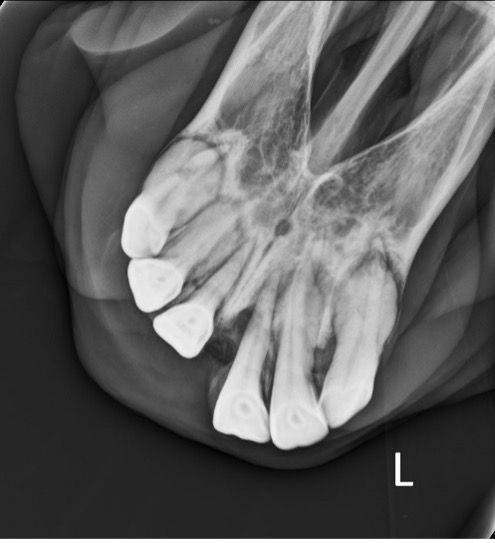

This condition primarily affects the intra-alveolar aspect of the teeth, most commonly incisors and canines, although cheek teeth can also be affected. Odontoclastic cells have been found to cause resorptive lesions extending into the cementum, enamel, dentin, and even the pulp, causing a marked loss of normal architecture in some teeth.13,14 This painful condition can present with absent to variable clinical signs, including masticatory problems. The veterinarian often makes the diagnosis by oral examination and radiographs (Figure 4) or advanced imaging. Findings upon oral examination include gingivitis, fistula formation, gingival recession, deposition of calculus, and swelling or abnormal tooth mobility. Tooth resorption and bulbous enlargement are frequent features on radiographic examination. Currently, surgical extraction of the affected teeth is the treatment option of choice. Supportive therapy with systemic antibiotics, anti-inflammatories, and local mouthwash has been shown to provide only short-term relief of symptoms at best.15